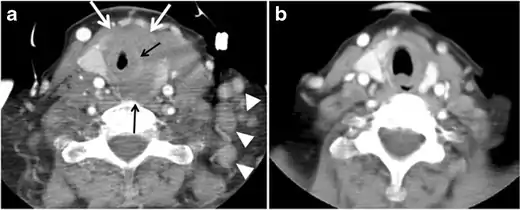

Thyroid lymphoma represents about 5% of thyroid malignancies. Non-Hodgkin's lymphoma is the most common type and can be secondary to generalized lymphoma or a primary tumour. Primary thyroid lymphoma usually pre-exists with Hashimoto's thyroiditis. On CT scans with and without contrast, lymphomas tend to have low attenuation values. Thyroid lymphomas have a variable appearance and mostly manifest as a solitary mass (80%). They may also manifest as multiple nodules (15% to 20%) or as a bulky mass replacing the entire gland with extra-thyroid extension (Figs. 11 and and12).12). The presence of cervical lymphadenopathy supports such a diagnosis. Although it is uncommon, tumour necrosis has been reported.[1]

Goiter

A goiter is an abnormal thyroid gland proliferation that manifests as multi-nodular, uni-nodular, or non-nodular diffuse glandular enlargement. A goiter is formed of solid matrix, colloid cysts, blood products, calcification, and fibrosis, and this heterogeneity may lead to variable appearances on a CT scan (Figs. 13, 1414 and and15)15). The US is more sensitive in evaluating thyroid nodules within a goiter; however, a symptomatic goiter may require surgical treatment with total thyroidectomy, and in this case CT plays an additional role in preoperative evaluation. Specific aspects for examination on a CT scan during the preoperative evaluation for goiter include extension, mass effect, and suspicious features of malignancy.[1]

Malignancy can coexist within the goiter and a CT scan may give a clue if there are abnormal cervical lymph nodes and/or signs of invasion. Retrosternal extension (Fig. 15) could affect the surgical approach, as a lower extent may require a partial or total sternotomy to facilitate complete resection. Therefore, the distance of the retrosternal extent from the sternal notch should be measured on a sagittal image.[1]

The interpreting radiologist should describe the mass effect, detailing its degree and direction of displacement of central structures, including the trachea, oesophagus, larynx, and pharynx. Attention should be directed to the upper extent of the goiter and structures immediately surrounding the thyroid gland, including the neuro-vascular structures, retropharyngeal space, and pre-vertebral space. The reporting radiologist should evaluate the vocal cords for symmetry and signs of vocal cord palsy.[1]